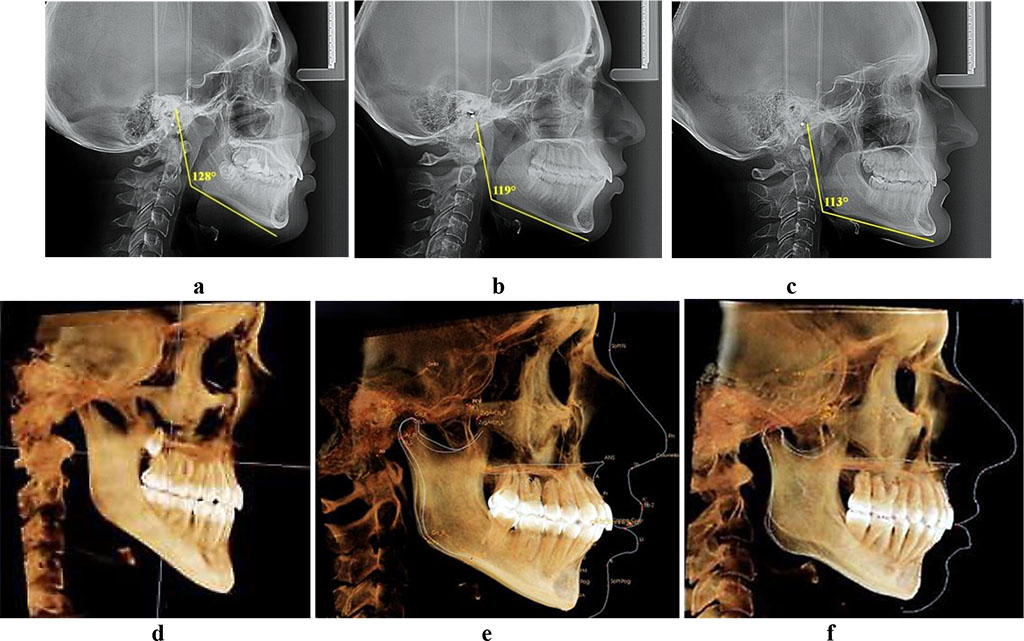

decrease in the mandibular angle (under 119°) (Fig.1).

Fig.

1. Teleroentgenograms and computed tomograms, patients with vertical

(a, d), neutral (b, е)

and horizontal (c, f) type of jaw growth.